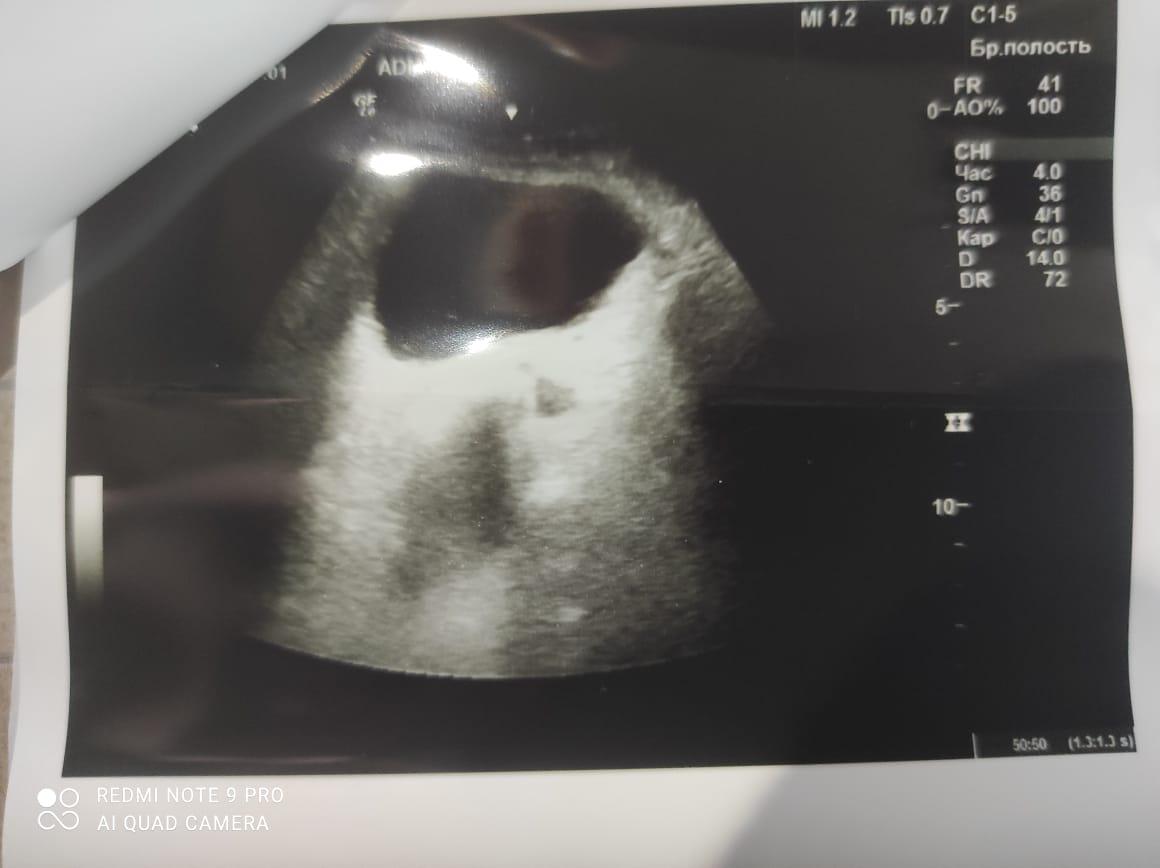

Здравствуйте! При наличии коралловидного камня правой почки(заключение УЗИ), можно предположить причиной боли нарушение уродинамики верхних мочевых путей), что, однако, не подтверждается результатами УЗИ почек( ЧЛС не расширена). Другая, наиболее вероятная возможная причина "боли в боку" - может быть патология опорнодвигательного аппарата. Необходимо проконсультироваться с неврологом и урологом очно, и согласовать возможность применения противовоспалительных, обезболивающих и спазмолитических препаратов - как первый шаг. В дальнейшем необходимо планировать возможное дальнейшее обследование и лечение. Удачи!